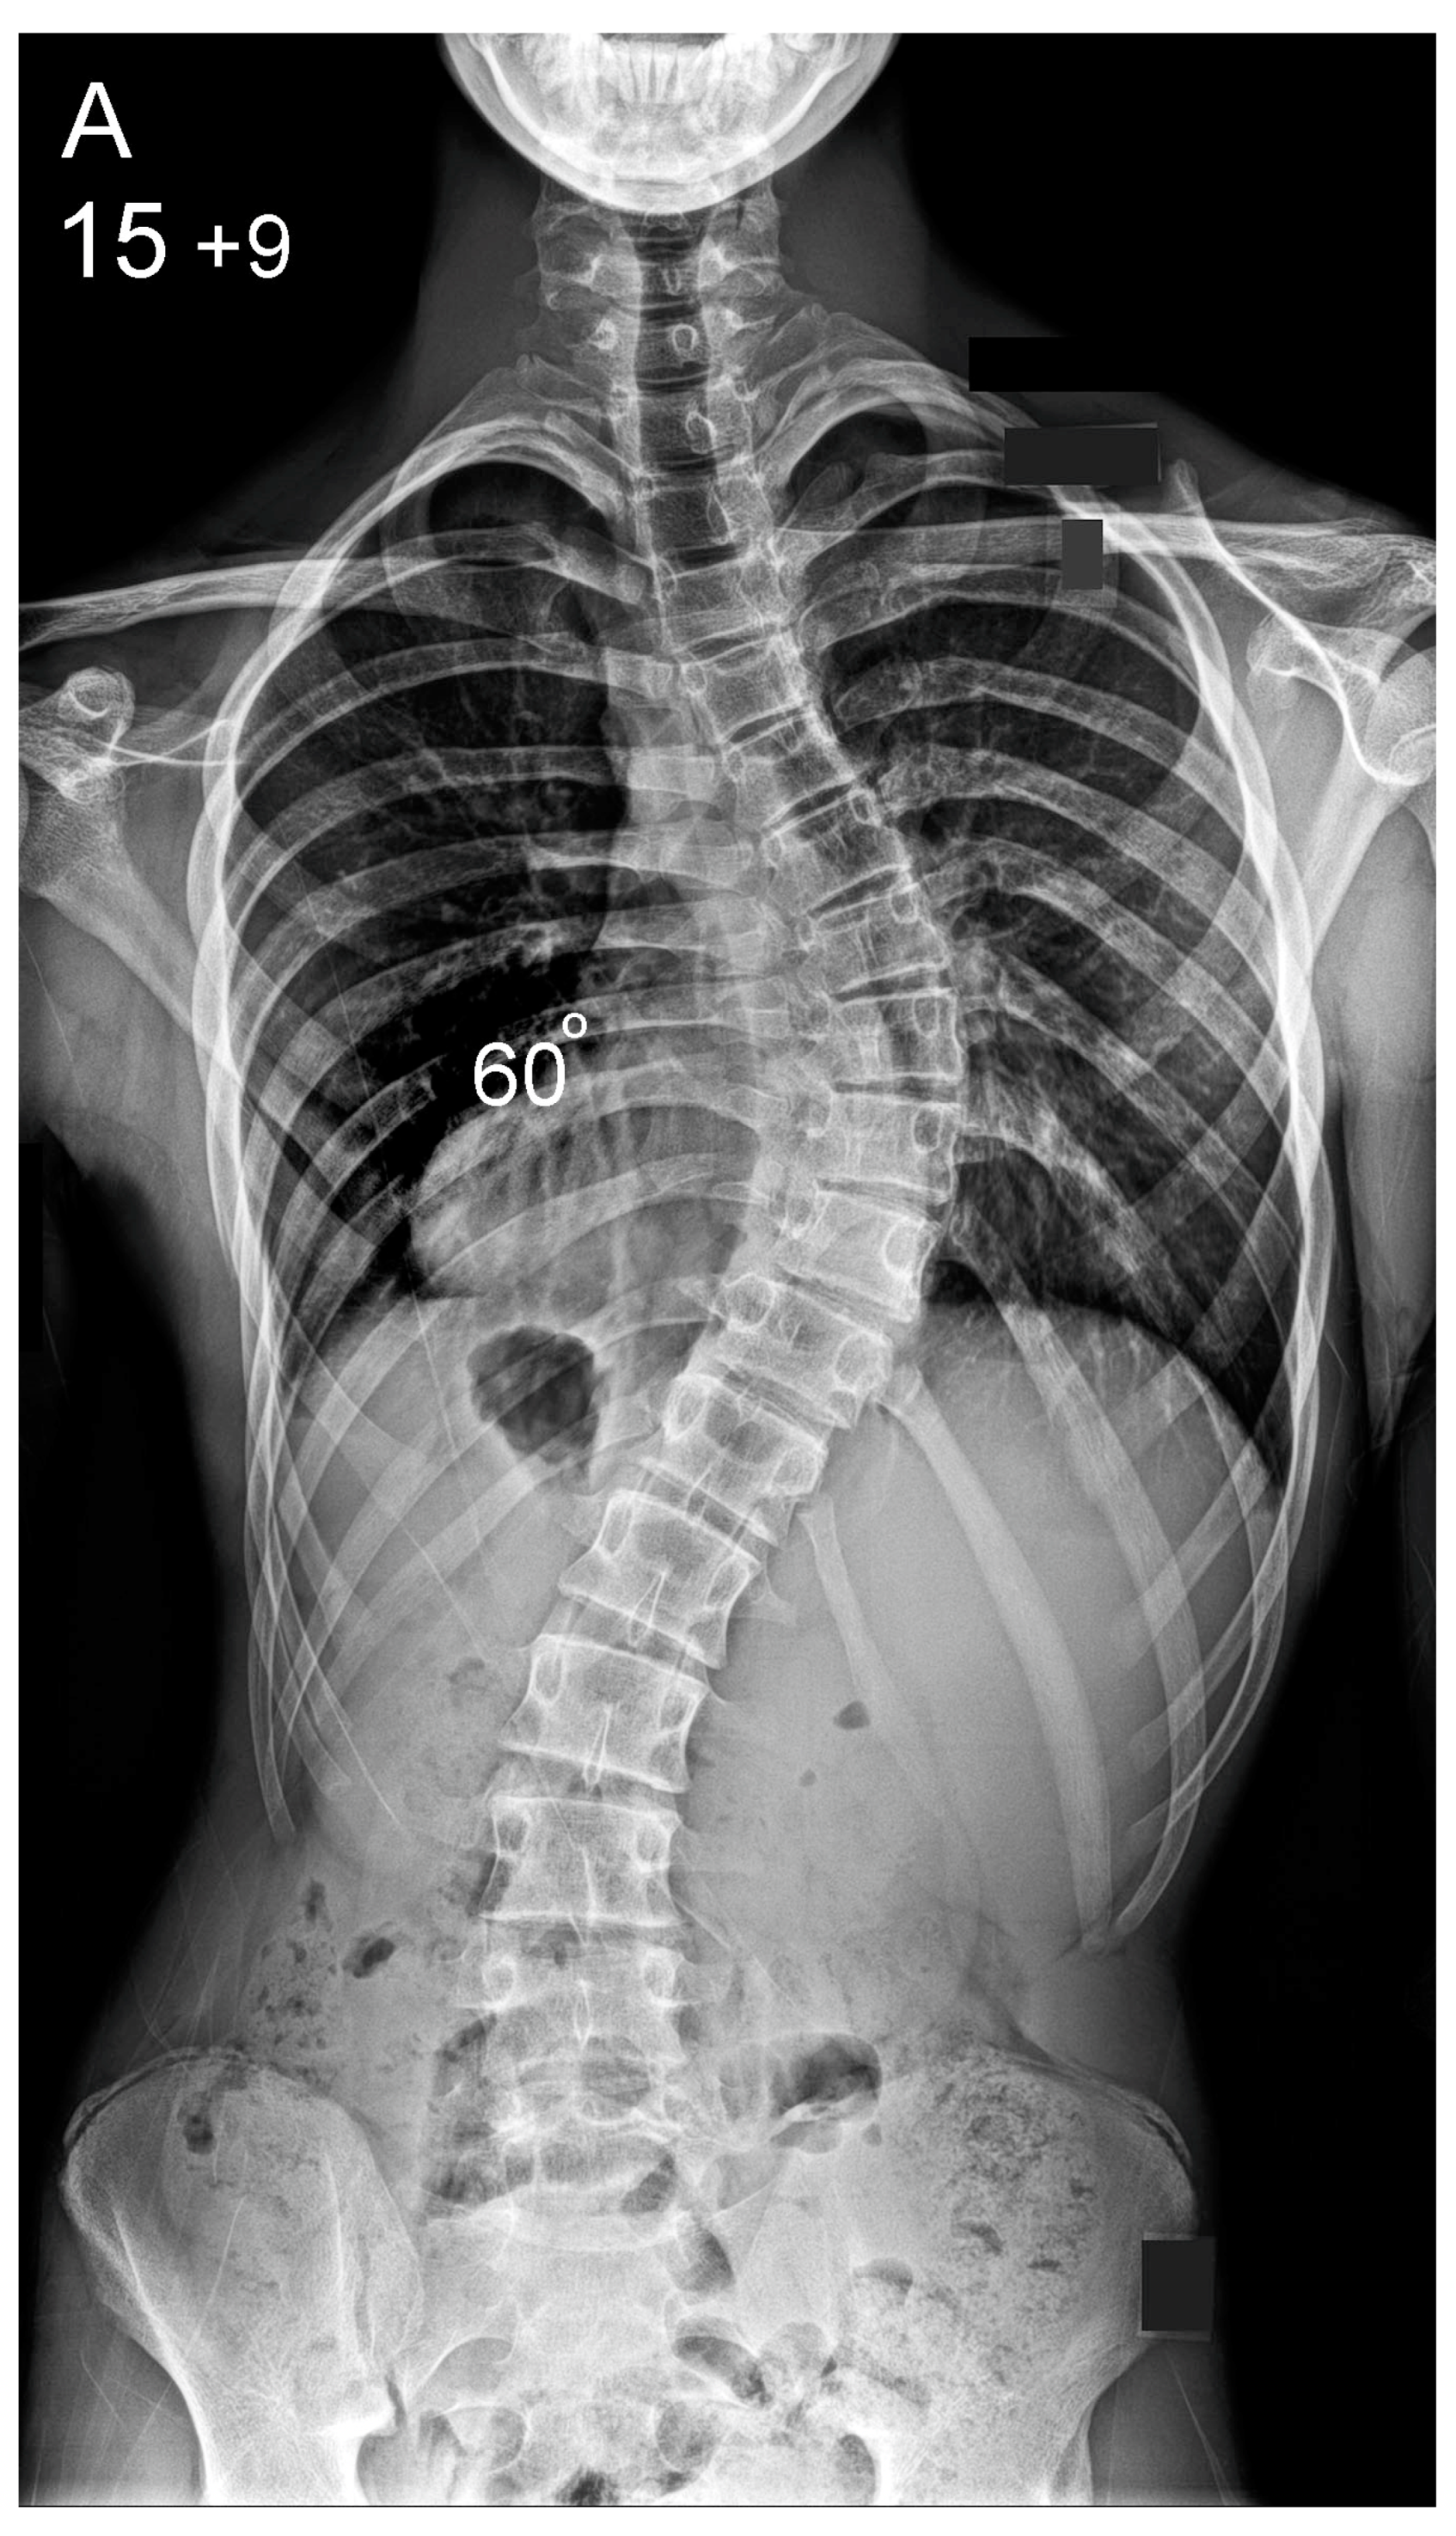

| Postoperative (°) | 14 (0–44) | 16 (2–40) | 0.1 |

| Correction Index (%) | 78 (42–100) | 75 (50–96) | 0.07 |

| Postoperative (cm) | 1.5 (0.4) | 1.9 (0–5) | 0.02 * |

| Correction Index (%) | 78 (37–100) | 70 (18–100) | 0.001 * |

| Postoperative (°) | 3.1 (0–13) | 6.3 (0–19) | <0.001 * |

| Correction Index (%) | 79.6 (67–100) | 73.1 (28–100) | 0.002 * |